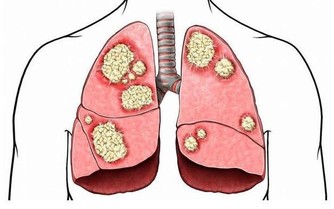

(圖片來源) 一位居住在倫敦的人的親身經歷 他去巴基斯坦開會的時候,突然胸口劇痛, 後來被醫院驗出來, 他的三條心血管已經被嚴重堵塞, 需要做搭橋手術。 手術的時間是一個月以後, 在這個期間,他去看一位治療師。 這位治療師給了他一個建議,結果卻十分驚人...! 食療一個月,心血管有驚人變化! 這位Hakim讓他自己在家中做食療,他吃了一個月。 一個月後他去同一家醫院做檢查, 發現三條血管幹乾淨凈, 原來堵塞的地方已經全通了。 為了讓更多的人受益, 他把自己的經驗放在網上分享, 他的前後兩張血管照片也放了在網上, 在照片中,服用食療之前與之後的分別, 連普通人也看得出來。

(圖片來源) 將成品存在有蓋的玻璃瓶中,放入雪櫃。 每天早飯前空肚服用一湯匙。 吃上一個月以後去醫院做次檢查, 會發現血管幹乾淨凈,堵塞的地方已經全通了! (文章來源) 心血管疾病很常見, 想打通血管,可以試試這個配方! 不過改變生活習慣更重要喔...!